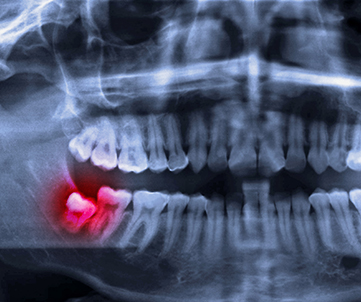

사랑니가 정상적으로 자라 날 공간이 부족한 경우 비스듬하게 누워 있거나 잇몸 속에 파묻힌 채로 자리 잡을 가능성이 높습니다. 이는 잇몸질환이나 충치를 유발할 수 있기에 조기에 치료를 진행하는 것이 좋습니다.

비스듬히난 사랑니 / 턱 뼈속에 완전히 묻힌 사랑니

→ 충치, 잇몸질환, 주변 어금니 손상, 턱 뼈 낭종, 신경자극을 유발할수 있음